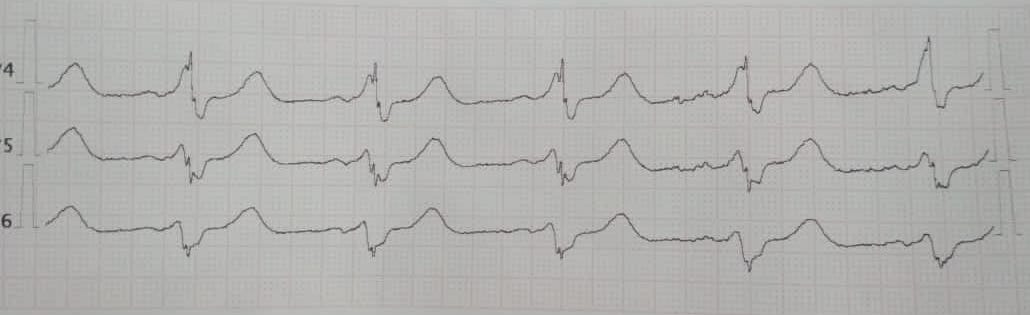

ФП и ВПВ

Обсуждалось здесь https://vk.com/club84409679?w=wall-84409679_9358%2Fall

ФП ВПВ

Обсуждалось здесь https://vk.com/club84409679?w=wall-84409679_13442%2Fall